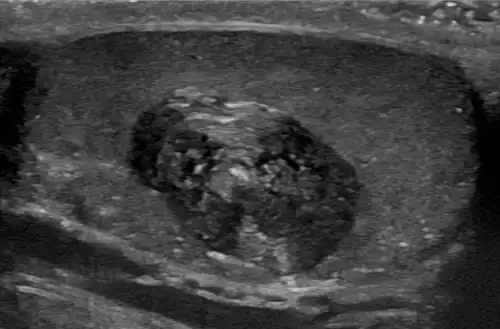

Epidermoid cyst in a testicle on ultrasound, with lamellated ("onion skin") appearance Epidermoid cyst in a testicle on ultrasound, with lamellated ("onion skin") appearance